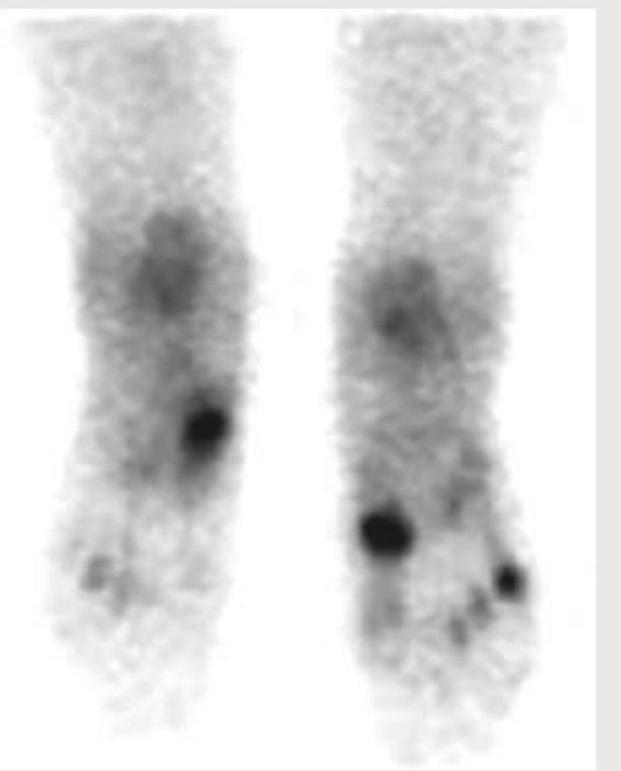

Explanation: ***Bone scintigraphy*** - This image displays a typical **bone scan** appearance, characterized by diffuse uptake throughout the skeletal system, with focal areas of increased tracer accumulation (hot spots) indicating increased bone turnover. - The visualization of the entire skeleton with this characteristic intensity and distribution of radioactive tracer is unique to **bone scintigraphy**. *Whole body MRI* - Whole body MRI images would exhibit detailed **anatomical structures** with varying signal intensities depending on tissue composition and MRI sequence, and would not show this uniform skeletal uptake pattern. - MRI is excellent for **soft tissue contrast** and bone marrow evaluation but does not produce the diffuse, radionuclide-based signal seen here. *Whole body CT scan* - A whole body CT scan provides highly detailed **cross-sectional anatomical images** based on X-ray attenuation, showing bone density and soft tissue. - It would not show the diffuse radionuclide uptake pattern characteristic of a bone scan but rather precise **structural details**. *Projectional radiography* - Projectional radiography (X-rays) would provide a 2D image of bone structures by showing differential absorption of X-rays, resulting in a distinct, shadow-like representation of bones. - It does not involve radioactive tracer uptake and therefore would not present this **diffuse uptake pattern** of the entire skeleton.

Explanation: ***18-F Fluoride*** - Among the listed PET tracers, **18-F Fluoride** is the bone-seeking radiotracer used for bone imaging - 18-F Fluoride PET provides high-resolution imaging of bone turnover and blood flow, and can detect stress fractures with high sensitivity - It localizes to areas of increased bone metabolism and osteoblastic activity, making it effective for detecting subtle stress injuries - **Note:** In routine clinical practice, **Tc-99m MDP (methylene diphosphonate)** is the standard tracer for conventional bone scintigraphy to detect stress fractures; however, among the PET tracers listed here, 18-F Fluoride is the appropriate bone imaging agent *FMISO (Fluoromisonidazole)* - **FMISO** is a **hypoxia tracer** used in PET imaging to identify areas of low oxygen tension - Primarily used in oncology to assess tumor hypoxia, not for bone or musculoskeletal imaging - Not indicated for evaluating stress fractures or bone metabolism *FLT (Fluorothymidine)* - **FLT** is a **proliferation tracer** that measures cellular DNA synthesis and proliferation - Mainly used in oncology to assess tumor growth and treatment response - Does not assess bone metabolism or detect stress fractures *64-Cu-ATSM* - **64-Cu-ATSM** is another **hypoxia tracer** used in PET imaging, similar to FMISO - Used to evaluate tissue hypoxia in cancer imaging - Not indicated for musculoskeletal injuries or bone metabolism assessment